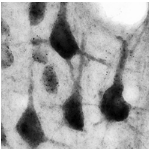

NAA and NAAG staining in rat brain